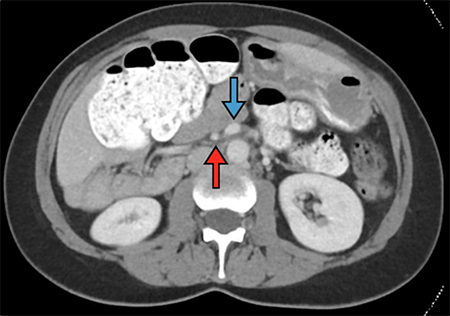

The patient, a 37-year-old woman, presented to the emergency department with four days of worsening abdominal pain. The pain was initially periumbilical in location, subsequently migrating to the right hemi-abdomen. The patient had had a longstanding history of nonspecific abdominal pain that had been labeled as irritable bowel syndrome by her primary care physician. The patient’s symptoms had been investigated seven years prior with an upper gastrointestinal contrast series. Per the patient, the study revealed "twisting" of her bowel, although no intervention was pursued at that time. She endorsed multiple loose bowel movements per day at baseline, but none since the onset of the acute pain. Vital signs were normal upon presentation, and examination revealed a soft, mildly distended abdomen, moderately tender to palpation in the epigastrium and right upper quadrant. Laboratory examinations were unremarkable. Given the patient’s tenderness on exam, a CT scan of the abdomen was performed which demonstrated the cecum abnormally positioned in the anterosuperior abdomen with multiple loops of small bowel displaced into the right lower quadrant (Figure 1). The duodenum did not clearly cross midline, the superior mesenteric vein (SMV) was seen to the left of the superior mesenteric artery (SMA), and swirling was seen in the small bowel mesentery (Figure 2).

Figure 2. Note the SMV (blue arrow) abnormally positioned to the left of the SMA (red arrow).